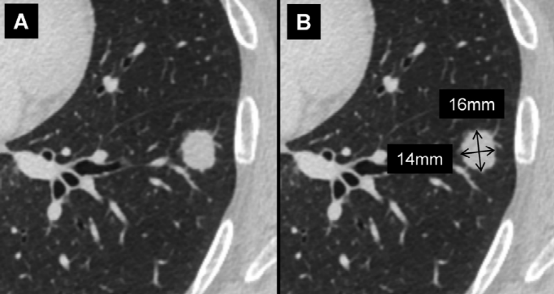

图A、左肺下叶实性结节。图B、最大长轴直径 (16mm,垂直箭头),垂直于长轴测量的最大短轴直径 (14mm,水平箭头)。结节的平均直径为15mm。

如肺小结节 (<10mm) 的尺寸应表示为同一平面内最大长轴和垂直最大短轴测量值的平均值。对于较大的结节或肿块 (>10mm),应记录长轴和短轴直径。因为该结节的平均直径>10mm,所以给出了长轴和短轴直径。